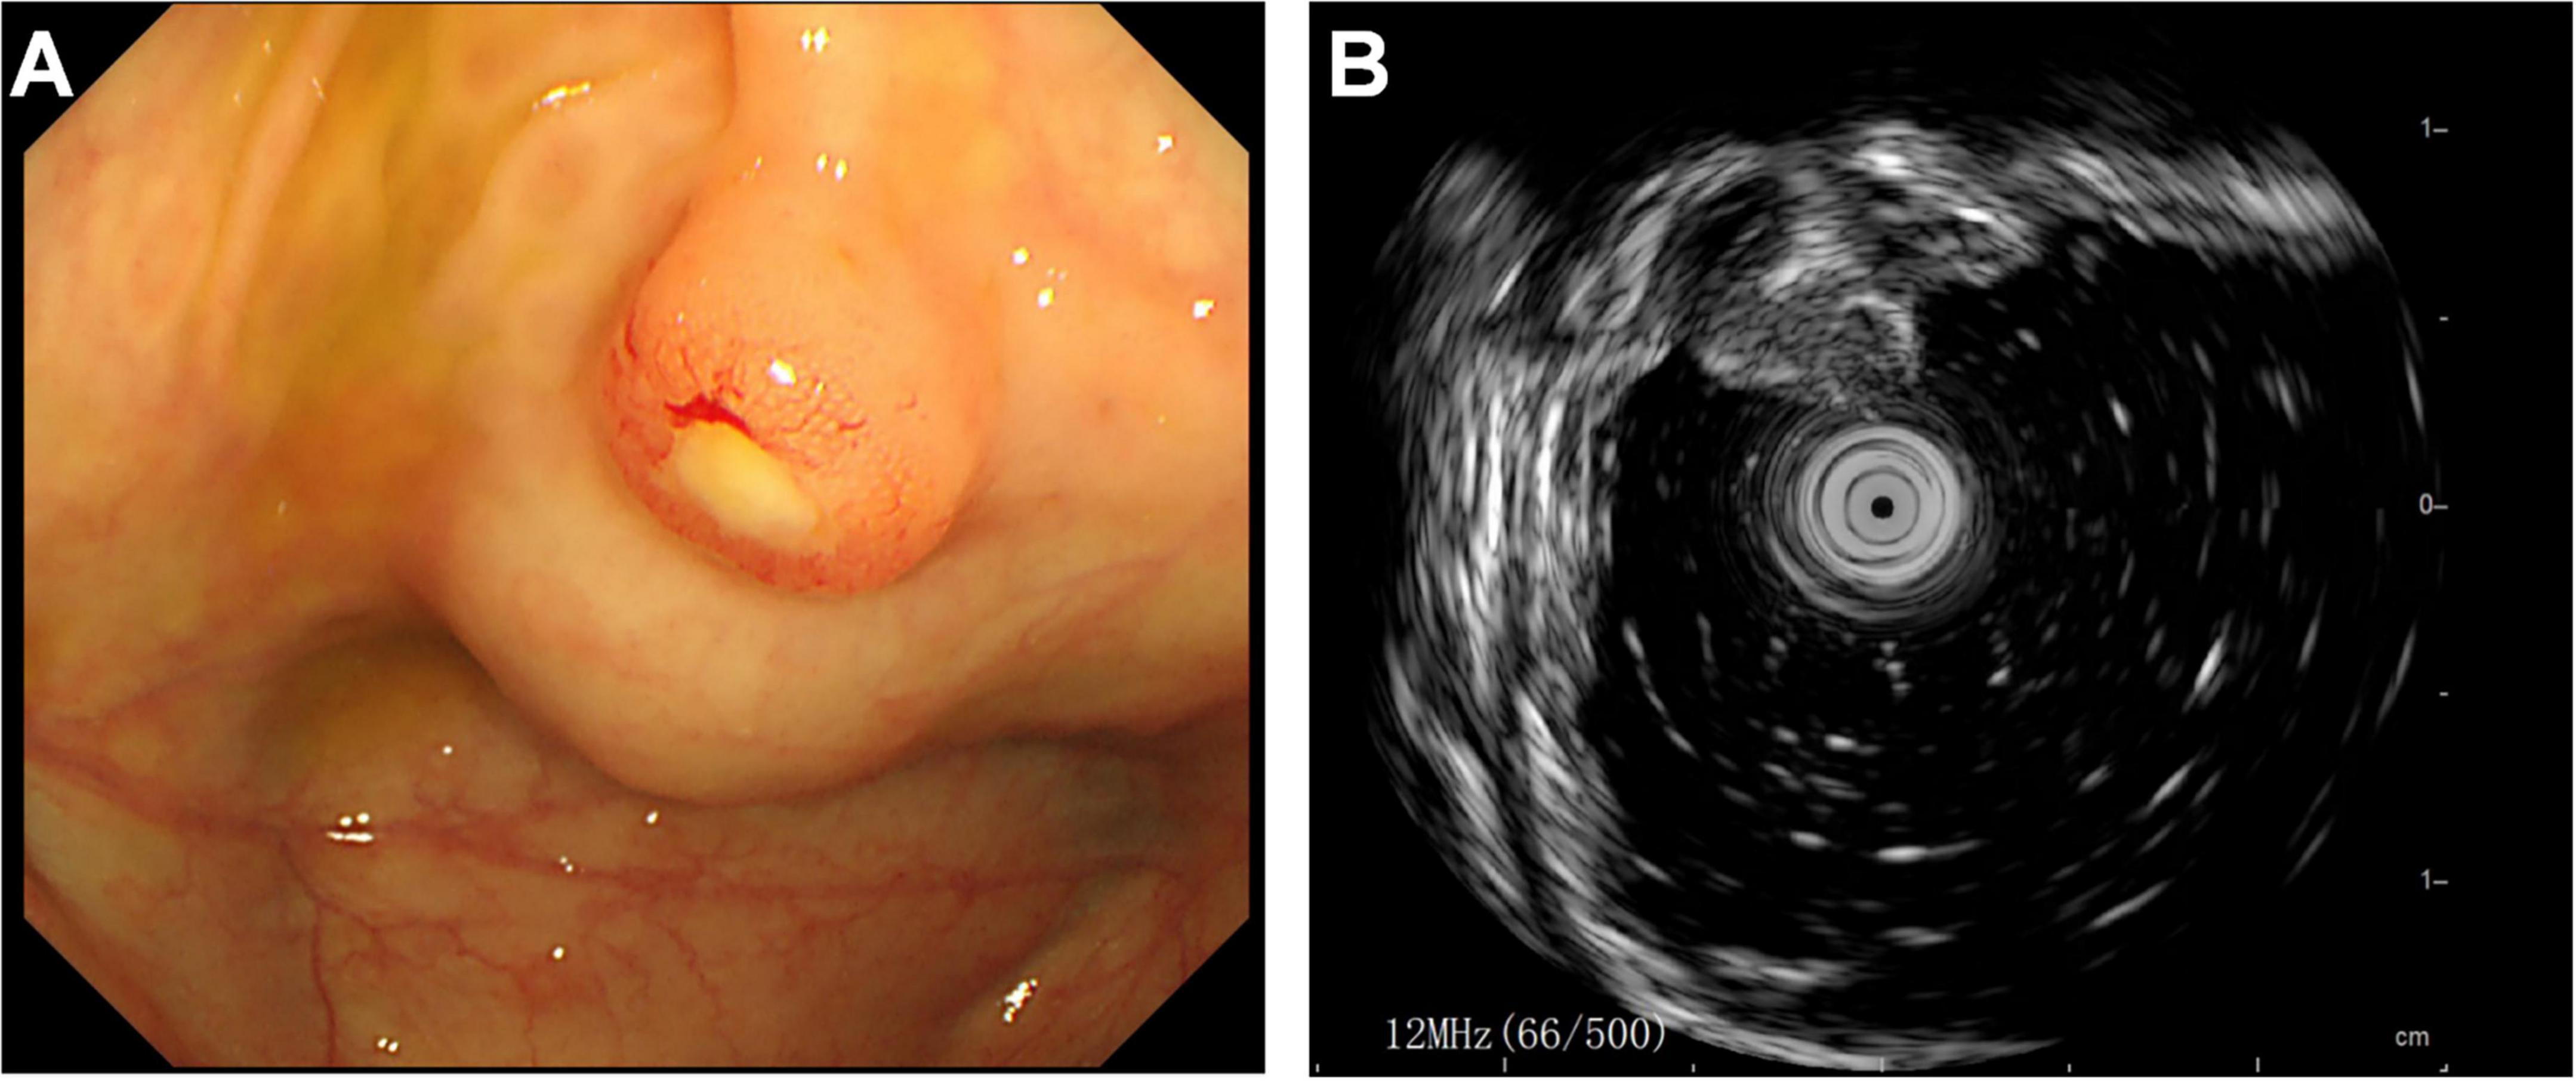

Subsequently, the patient underwent endoscopic evaluation. Endoscopy demonstrated chronic gastritis, gastric polyps, and duodenal papillae enlargement, with histopathology confirming benign glandular polyps. Endoscopic ultrasound (Figure 3) identified a 6.4 mm × 5.5 mm heteroechoic submucosal lesion protruding from the appendiceal orifice. Biopsy confirmed a neuroendocrine tumor (Figure 4) with immunohistochemical profile (G2 grade, Ki-67 ∼5%): SSTR2(+), Rb(+), P53 (wild expression pattern), Melan-A(−), HMB45(−), CD56(+), CgA(+), S100(−), SOX-10(−), Syn(+), E-cad(cell membrane positive), CEA[P](+), CEA[M](+), CK(+). Bronchoscopy demonstrated neoplastic obstruction in the left lower lingular segment with ultrasonographically evident lymph node clusters (stations 7/11). Histopathology (Figure 4) confirmed atypical carcinoid tumor (Ki-67 ∼30%) exhibiting CK(+), CgA(+), Syn(+), CK7(+), CD56(+), TTF-1(8G7G3/1)(+), with negative SSTR2 and lineage-specific markers. The station 7 and 11 Lymph node biopsies confirmed metastatic atypical carcinoid. Cytologic analysis revealed moderate cellular atypia without infectious organisms.

FIGURE 3

Endoscopic evaluation of appendiceal neuroendocrine tumor. (A) Colonoscopic visualization of a hemispherical protrusion at the appendiceal orifice. (B) Endoscopic ultrasound revealing a heterogeneous predominantly hypoechoic lesion (calipers) originating from the submucosal layer.